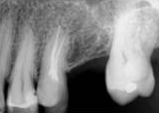

antes depois